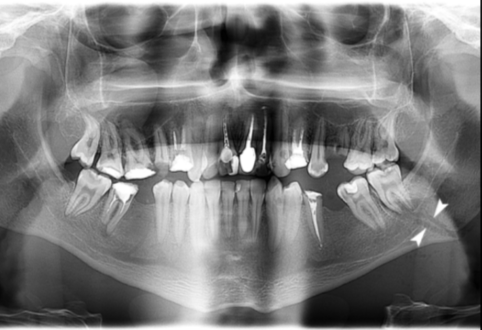

Dental Radiographs

X-rays used to assess trauma to the teeth and jaw.

Periapical Radiograph

An X-ray that shows the whole tooth, its roots, and surrounding bone.

Injuries affecting the maxilla and facial bone structures.

Alveolar Fracture

Fracture involving the alveolar bone that supports the teeth.

Mandibular Fracture

Break in the lower jawbone.

imaging for fractures

PA to CBCT

fractured maxilla